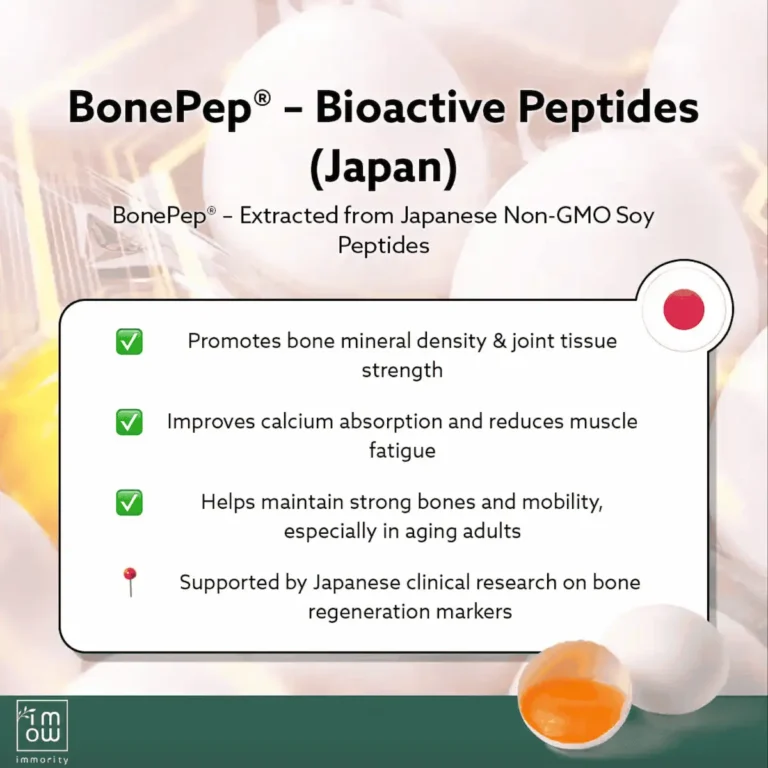

Peptide derived from egg yolk protein, specially designed to improve bone strength and density.

- Promotes healthy bone density

- Strengthens joints

- Helps prevent osteoporosis & 2x stronger than calcium.

- Complements cartilage repair